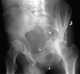

Acetabular fracture

Fractures of the acetabulum occur when the head of the femur is driven into the pelvis. This injury is caused by a blow to either the side or front of the knee and often occurs as a dashboard injury accompanied by a fracture of the femur.The acetabulum is a cavity situated on the outer surface of the hip bone, also called the coxal bone or innominate bone. [Source: Wikipedia ]